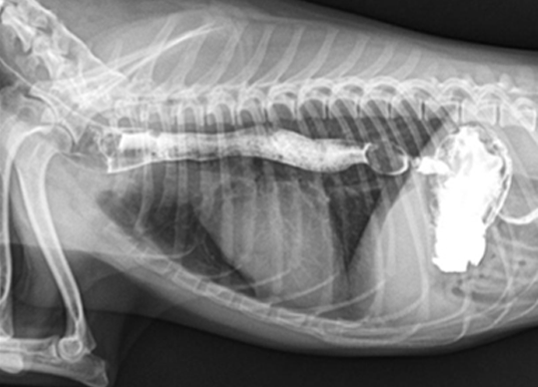

일반 X-Ray 촬영검사

흉부, 복부, 두부, 근골격계, 척추 촬영을 통해 환자 전반에 걸친 기본적인 정보를 획득할 수 있는 손쉬운 진단방법입니다. 본원 영상의학과의 X-선 검사장비는 디지털 검사장비를 도입하여 영상의 구현과 검사시간을 단축하였으며, 촬영시간은 물론 촬영 대기시간, 촬영에서 진단까지의 시간이 단축되어 환자 서비스 향상을 이룰 수 있습니다. 만일 촬영 후에 사진이 만족스럽지 않은 경우라 하더라도 촬영 후에 농도조정이 가능하기 때문에 불필요한 재촬영을 대폭 줄일 수 있습니다.